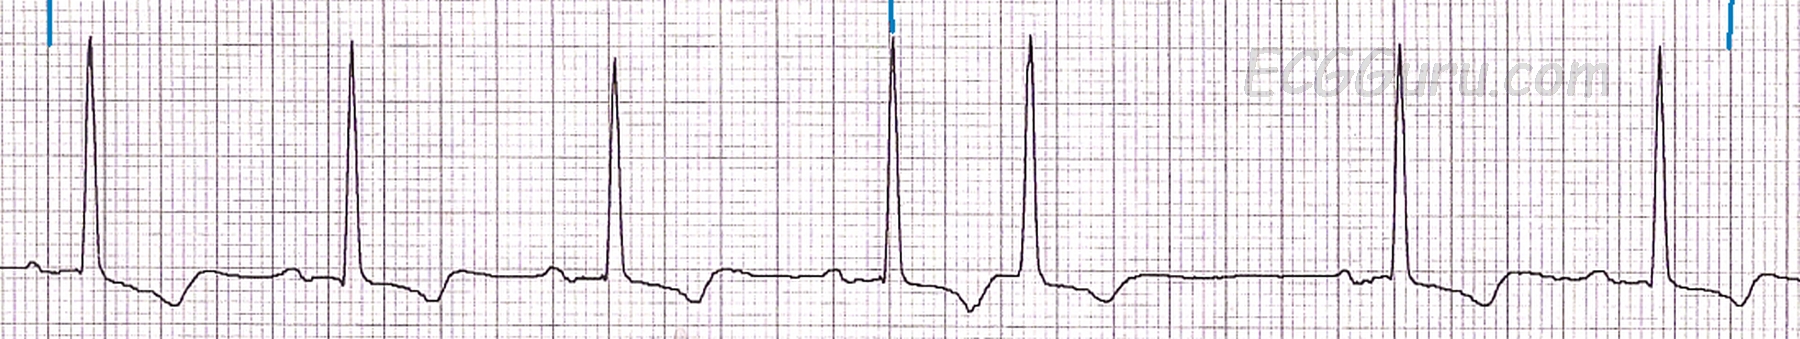

This strip shows a supraventricular tachycardia, rate 196 bpm, after adenosine was administered to the patient.  The PSVT breaks, and an irregular rhythm composed of sinus beats and premature atrial contractions ensues.  This is common after medical cardioversion. The patient later settled into a normal sinus rhythm.  The abrupt change from a fast, regular rhythm to a slower, irregular rhythm is evidence that the tachycardia was due to a reentrant circuit, and not sinus tachycardia.